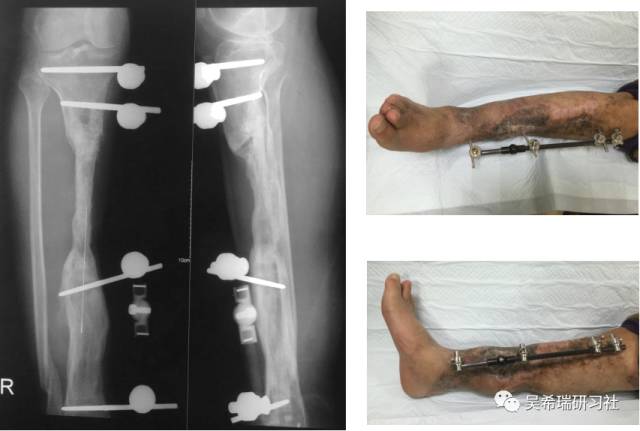

病例8

双下肢车祸外伤保肢的理由是足底皮肤好

TIPS:清创&盐水冲洗(不用双氧水)VSD骨水泥技术&开放植骨单边外固定架(下胫腓联合固定)早期下地 生理应力 + 机械应力游离植皮 / 不用皮瓣清创时游离皮质骨去除胫跖骨牵引技术防治&纠正足下垂